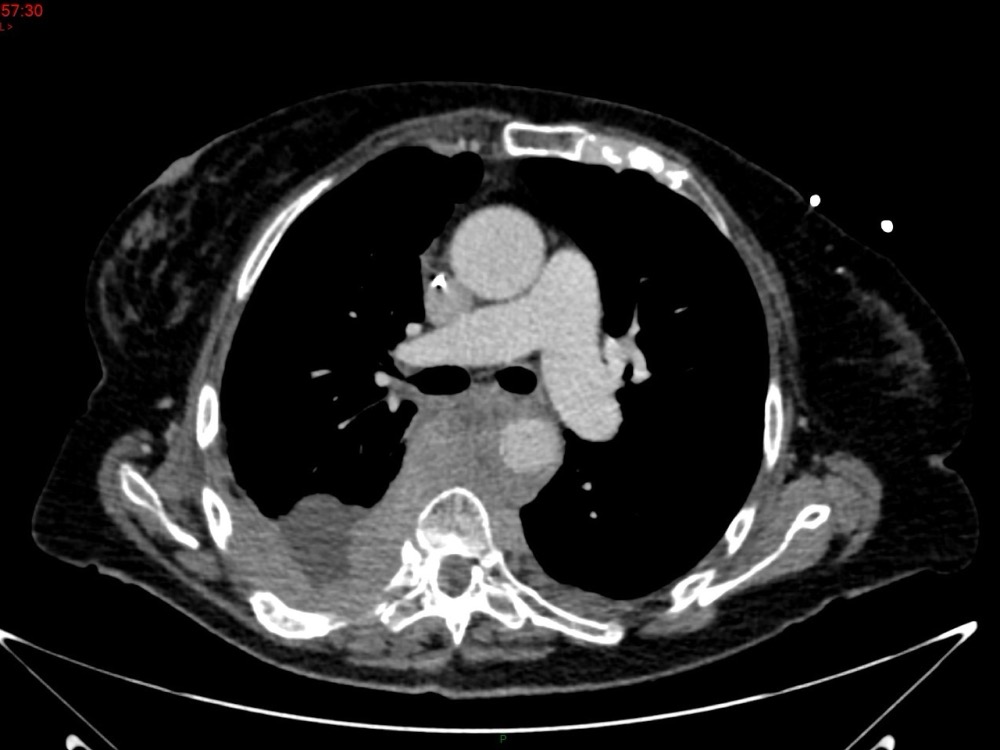

Marie Pauline Talabard 11/01/2023